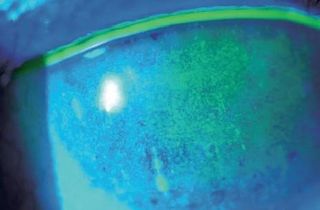

Le syndrome sec peut provoquer des kératites ponctuées superficielles

et des abcès de la cornée. Au stade ultime des ulcères de cornée

Le syndrome sec peut être détecté par votre ophtalmologiste à l'aide d'un biomicroscope

et de l'instillation de  gouttes de fluorescéine. De nombreux examens existent aussi pour préciser l'intensité et l'origine de l'atteinte (NIKBUT, méibographie, étude du ménisque lacrymal etc...)